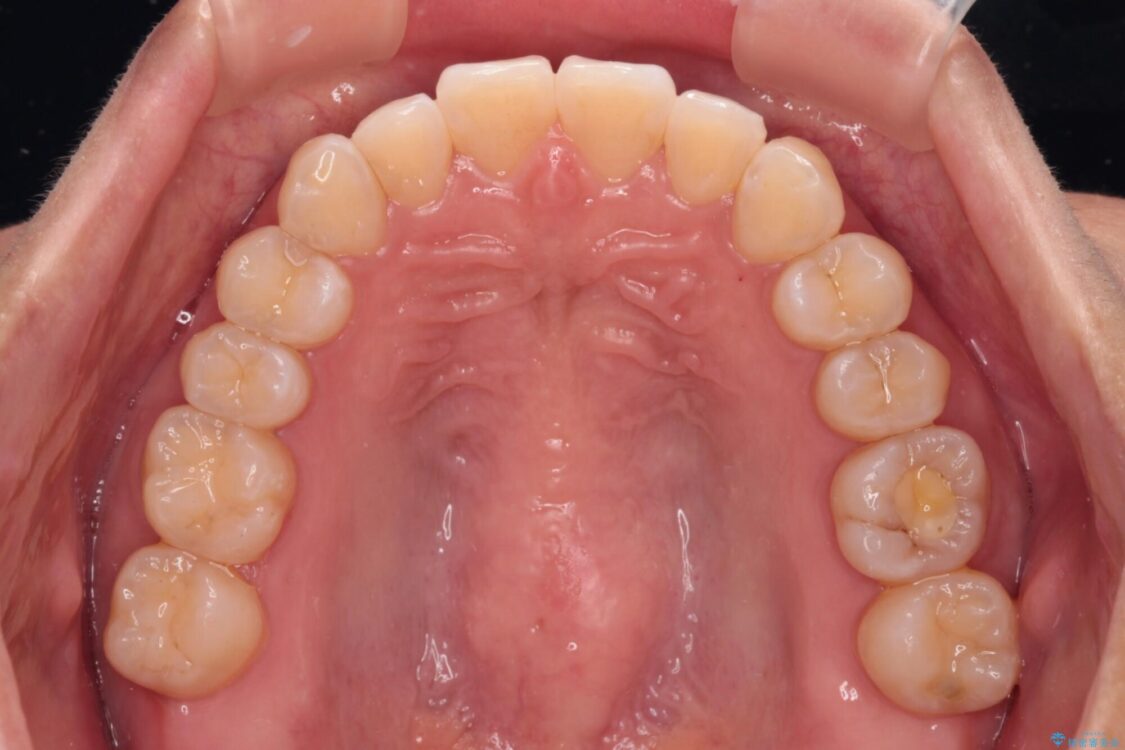

治療後

• 【モニター】前歯のデコボコをインビザラインで改善 治療後画像